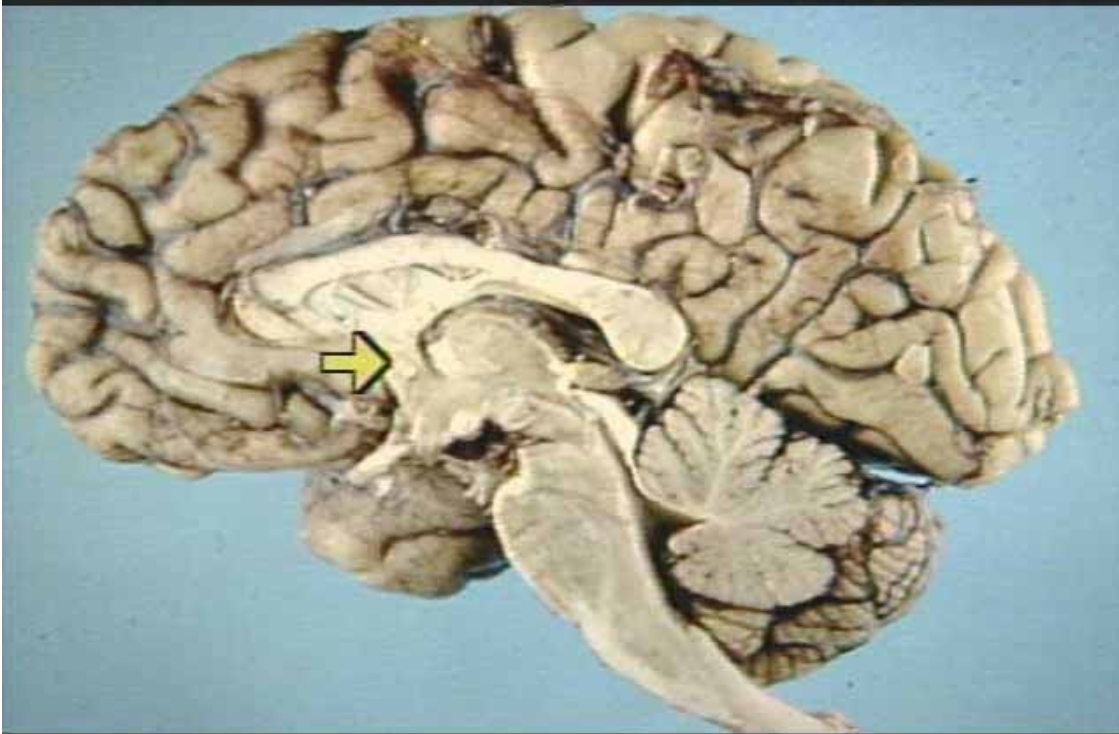

What is the arrow pointing at?

Anterior Commissure (Real Medial View of Brain)